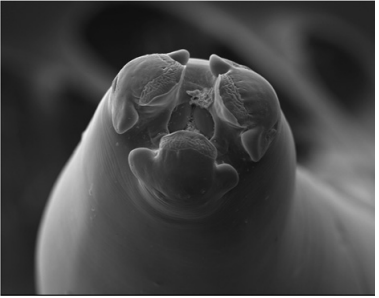

As técnicas de microscopia evoluíram muito desde as primeiras análises de estruturas biológicas realizadas pelo inglês Robert Hooke e pelo holandês Anton Van Leeuwenhoek, no século XVII.

Considerando-se as três figuras precedentes, selecione a opção que apresenta, respectivamente, a modalidade de microscopia empregada na obtenção de cada uma delas.